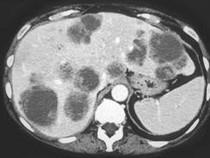

问题 男,54岁,患者一年前行结肠癌手术,癌胚抗原增高,影像检查如图,最可能的诊断是 ( )

选项 A.多发结节性肝癌 B.结肠癌肝转移 C.多发性肝脓肿 D.多发性肝囊肿 E.肝淋巴瘤

答案 B